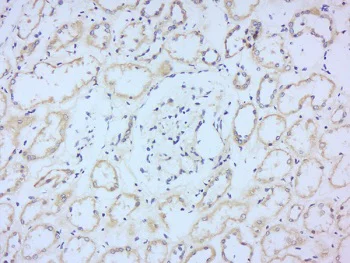

Immunohistochemistry (Formalin/PFA-fixed paraffin-embedded sections) - Anti-2B4 antibody (AB217335)

Immunohistochemical analysis of paraformaldehyde-fixed and paraffin-embedded Human kidney tissue labeling 2B4 with ab217335 at 1/200 dilution, followed by conjugation to the secondary antibody and DAB staining.